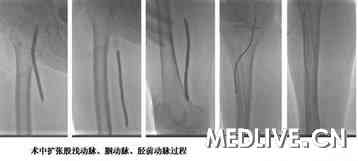

图2 扩张下肢动脉过程

术中造影显示,右侧股浅动脉闭塞,胫前、胫后长段闭塞,TACS D级,行球囊扩张术+支架置入+溶栓术。